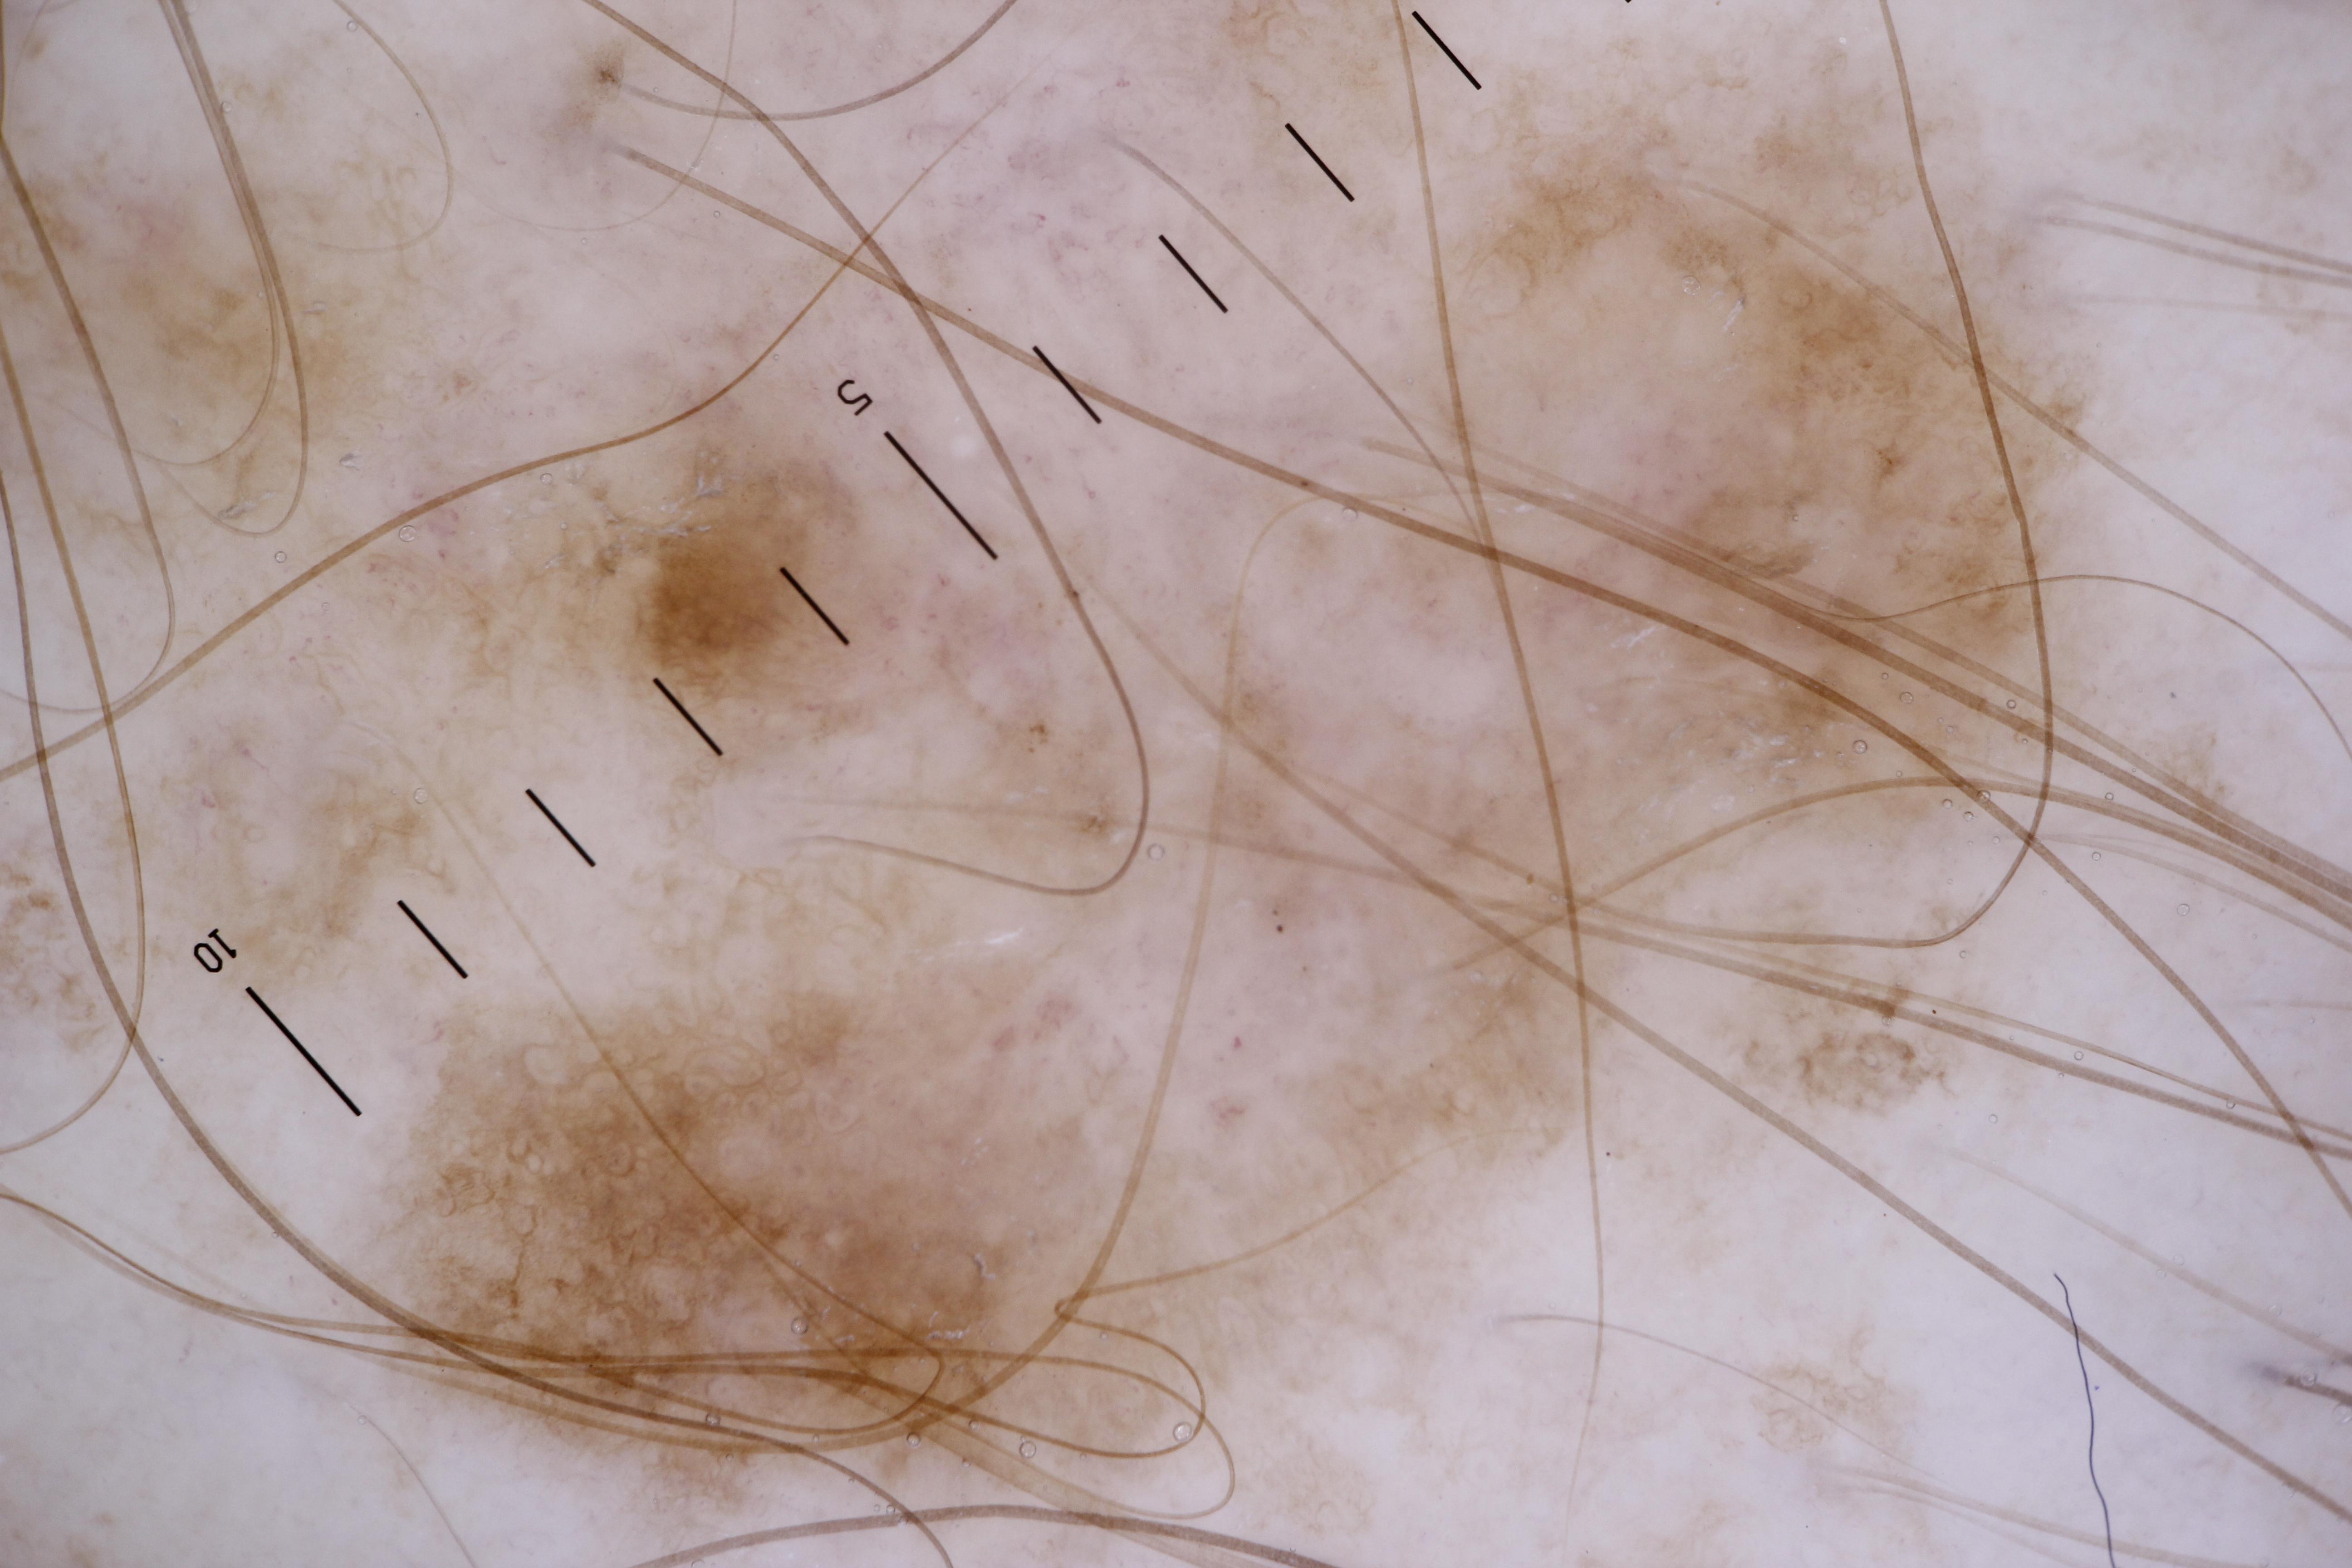

{

"acquisition_day": 990,

"age_approx": 80,

"anatom_site_general": "posterior torso",

"concomitant_biopsy": false,

"diagnosis_1": "Benign",

"diagnosis_confirm_type": "serial imaging showing no change",

"fitzpatrick_skin_type": "II",

"image_type": "dermoscopic",

"lesion_id": "IL_8392202",

"patient_id": "IP_1564172",

"sex": "male"

}